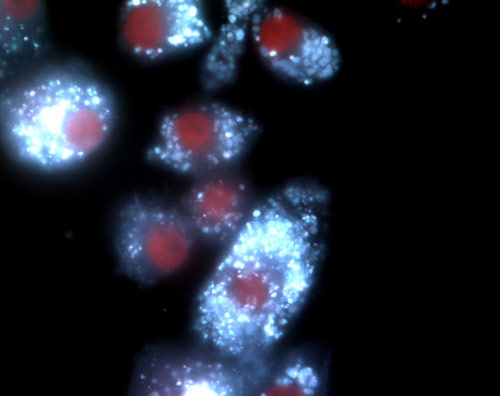

Highly commended: Killer Cholesterol by Dr Yichuan Wen and Dr David Leake, University of Reading. Immune cells called 'foam cells' are found in the arteries of people with atherosclerosis. The white specks are cholesterol, which can cause changes that lead to heart attacks and strokes Photograph: Dr Yichuan Wen and Dr David Leake/University of Reading/The British Heart Foundation